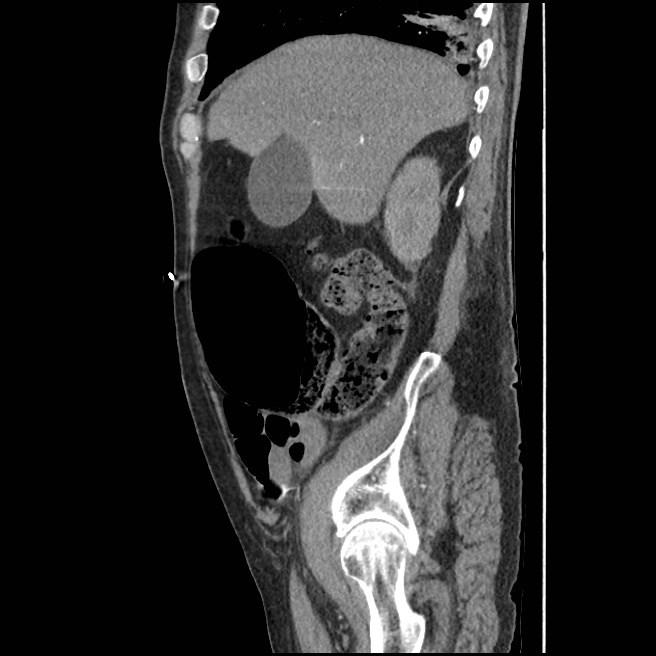

What is this?

Caecal bascule

Dr Matt A. Morgan◉ and Assoc Prof Frank Gaillard◉◈ et al.

Caecal bascule is an uncommon type of caecal volvulus in which the caecum folds up over itself in an anteromedial orientation. In contrast to the more common forms of volvulus, there is no axial “twisting” component 4. A caecal bascule may occur in the setting of a large and mobile caecum and can result in closed obstruction involving the caecal pole and appendix.

Clinical presentation and treatment are not significantly different from the more common axial caecal volvulus.

Radiographic features

Plain radiograph

An abdominal radiograph of a patient with a caecal bascule will demonstrate a distended air-filled caecum located centrally within the abdomen. Occasionally the appendix is distended and air-filled, improving one’s confidence that the caecum is obstructed more distally.

Importantly, as the terminal ileum is usually not involved in the volvulus, the small bowel is not obstructed.